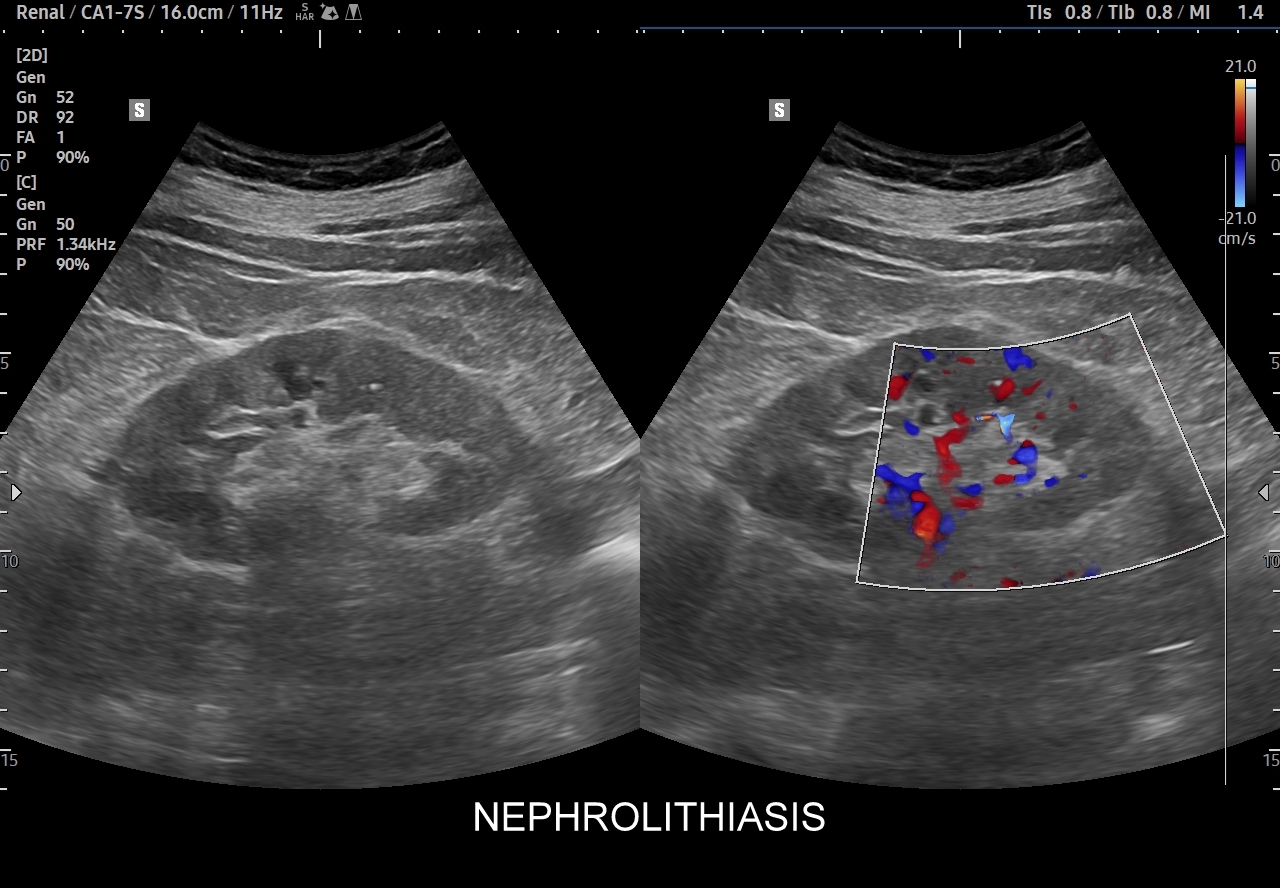

Badania obrazowe służące wykrywaniu kamicy moczowej to badanie RTG, CT, lecz przede wszystkim badanie USG. W badaniu USG nerek w prezentacji B kamica nerkowa widoczna jest w sytuacji, gdy złogi są odpowiednio uwapnione, odpowiednio duże oraz nie zlewają się z zatoką tłuszczową miedniczki nerki. Zasadniczo złogi w trybie B będą widoczne wyraźniej, gdy położone są w miąższu nerki; z kolei w miedniczce nerkowej, gdy są na tyle duże, że dają artefakt cienia. Czasem w celu uwidocznienia złogu przydatne jest wyłączenie wspomagania typu x-beam.

Ważnym trybem pomocniczym jest color-Doppler, w którym to trybie uzyskuje się tzw. artefakt migotania, często nawet na bardzo drobnych złogach niewidocznych w trybie B. Uzyskanie efektu migotania jest niestety zależne o jakości aparatury USG, a także od ustawień Dopplera i software’u.